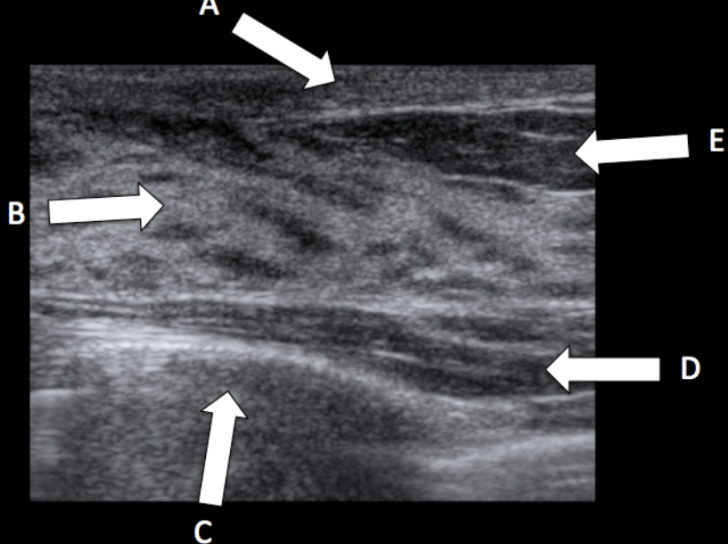

A - skin

E - fatty tissue

B - fibroglandular tissue

D - pectoralis major muscle

C - rib